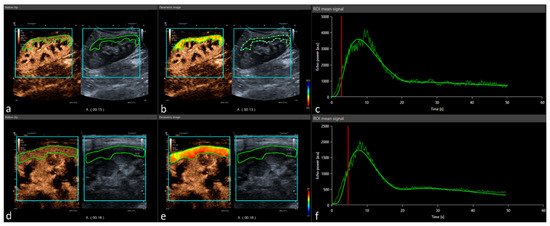

2.2. Imaging Protocol

2.3. Perfusion Quantification